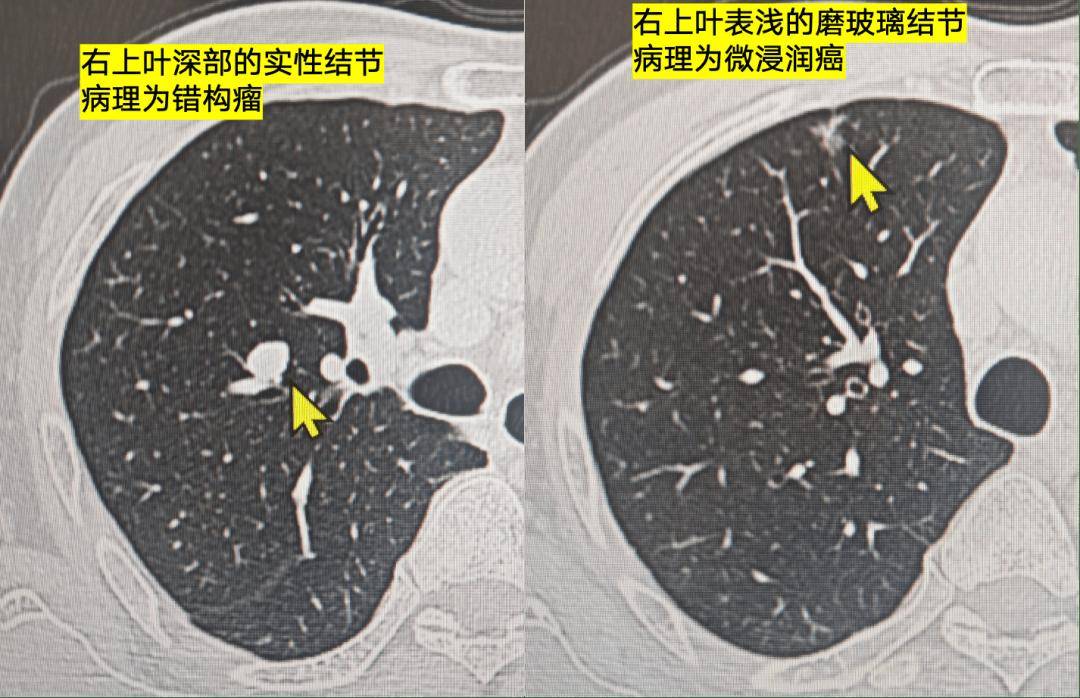

男性,50+岁,右肺上叶磨玻璃结节+右上叶实性结节

磨玻璃结节很典型,像 早期肺癌

实性结节边界清晰,内部有脂肪密度,像 错构瘤

病理显示,磨玻璃结节为微浸润癌,实性结节为错构瘤。